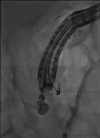

Every trick in the book: EUS angiotherapy for management of refractory bleeding secondary to a complicated duodenal ulcer in a patient with Roux-en-Y gastric bypass